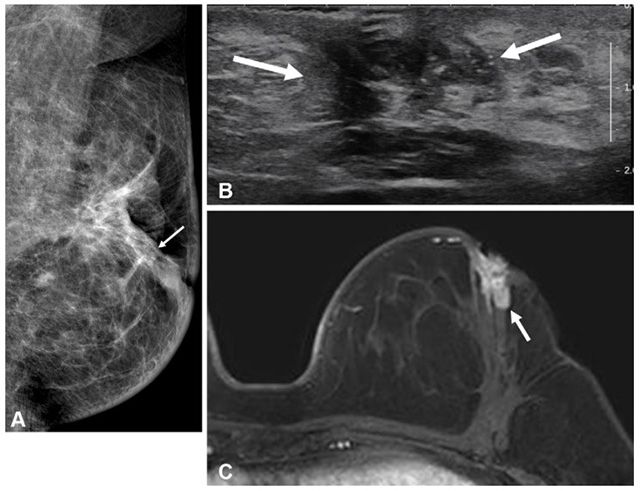

- ▲ 수술 전 MRI 검사를 시행하지 않은 50세 이하 유방암 환자의 수술 2년 후 영상. (A) 유방촬영술, (B) 초음파, (C) MRI. 동측 유방 내 재발 병변(화살표)이 관찰된다. /이미지 제공=서울대병원

분석 결과, 전체 재발률과 생존율에는 유의한 차이가 없었지만, 동측 유방 내 재발률은 MRI군 1.6%, 비MRI군 3.3%로 절반 수준이었다.